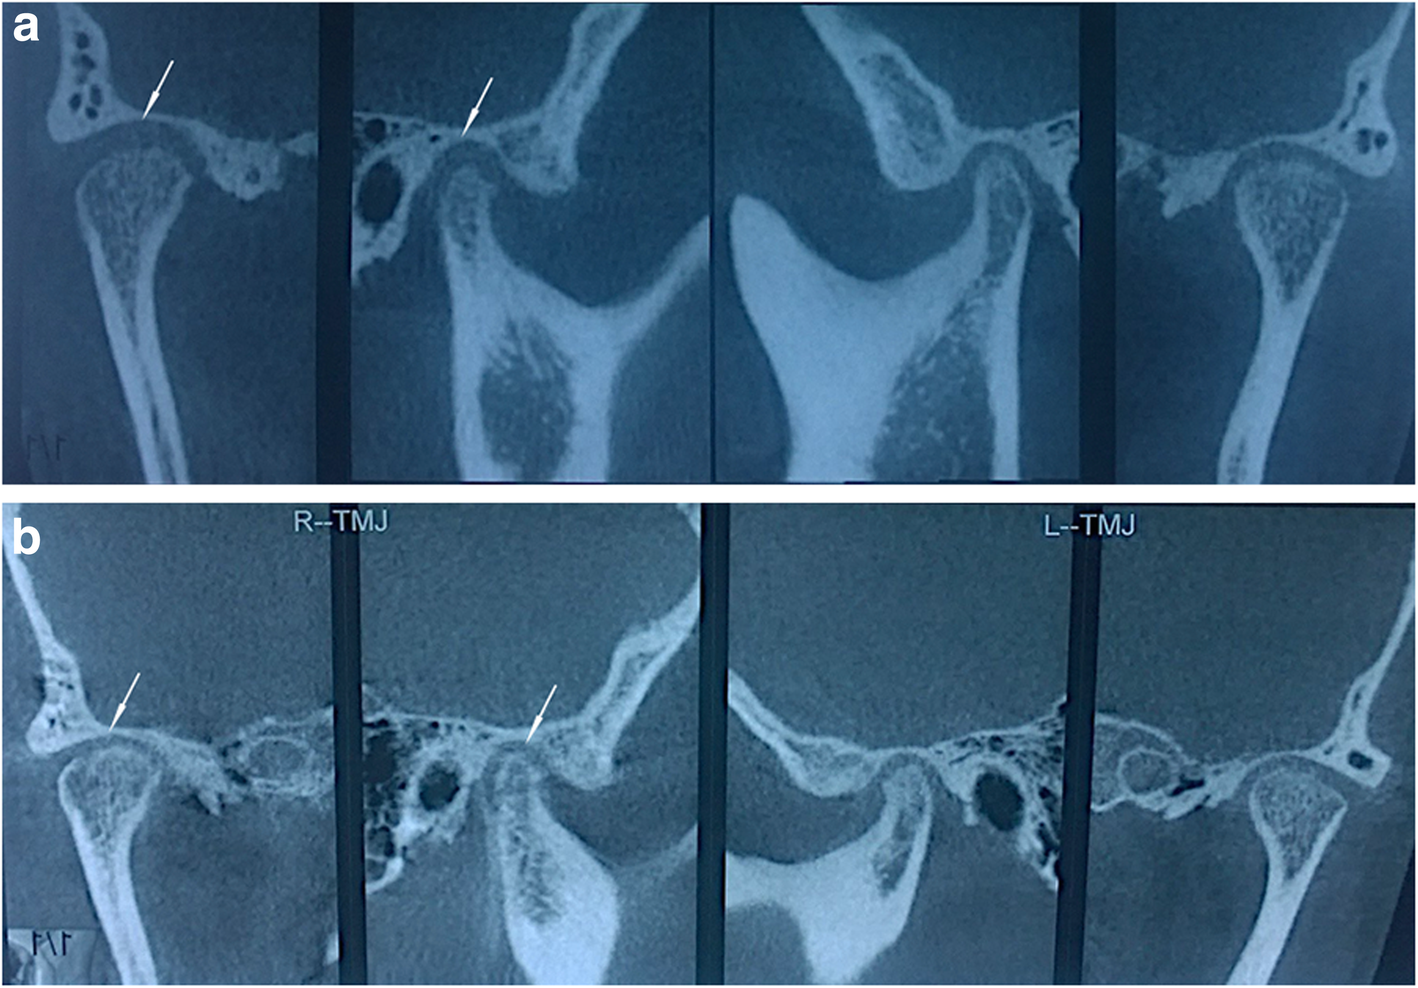

Fig. 3From: Application of auriculotemporal nerve block and dextrose prolotherapy in exercise therapy of TMJ closed lock in adolescents and young adultsThe figures show the pre- (a) and post-treatment (b) CBCT images of the TMJsBack to article page